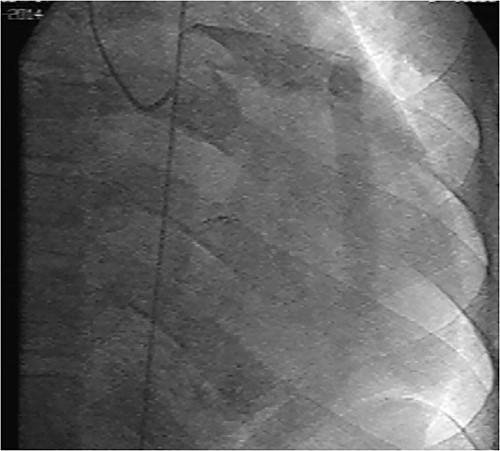

Initial physical examination showed stable vital signs. Auscultation found systolic murmurs of mitral and tricuspid regurgitations. There were no peripheral edema or other signs of heart failure. Abdominal examination revealed no tenderness, hepatomegaly or ascites. Electrocardiogram at admission showed sinus rhythm with no conduction abnormalities or signs of ischemia. Chest radiograph found an enlargement of the cardiac silhouette. Routine blood tests were normal. Transthoracic echocardiography (TTE) found a bi-atrial cystic structure, which we initially suspected to be a hydatid cyst as cystic echinococcosis is highly endemic in Morocco. Color Doppler showed a massive shunt with blood coming into the right atrium (RA) from an unknown source (Fig. 1). Cardiac magnetic resonance imaging (CMR) showed a bilobed cystic lesion hypointense on T1 and T2 sequences, with the same signal as cardiac chambers, located below and behind the left atrium (LA). The superior lobe was 48-mm wide and the inferior lobe 65-mm wide. On the peripheral wall of this structure, a giant circumflex artery (LCX), with a right atrial shunt, was present (Fig. 2). Coronary angiography (CA) along with computed tomography angiography (CCTA) confirmed the bilobed circumflex saccular aneurysm and CAF (Figs 3 and 4).

CCTA (with 3D reconstruction) showing the CAF alongside a bilobed saccular aneurysm fed by a giant circumflex artery, next to the RA. A, aneurysm of the circumflex artery; LCX, circumflex artery.